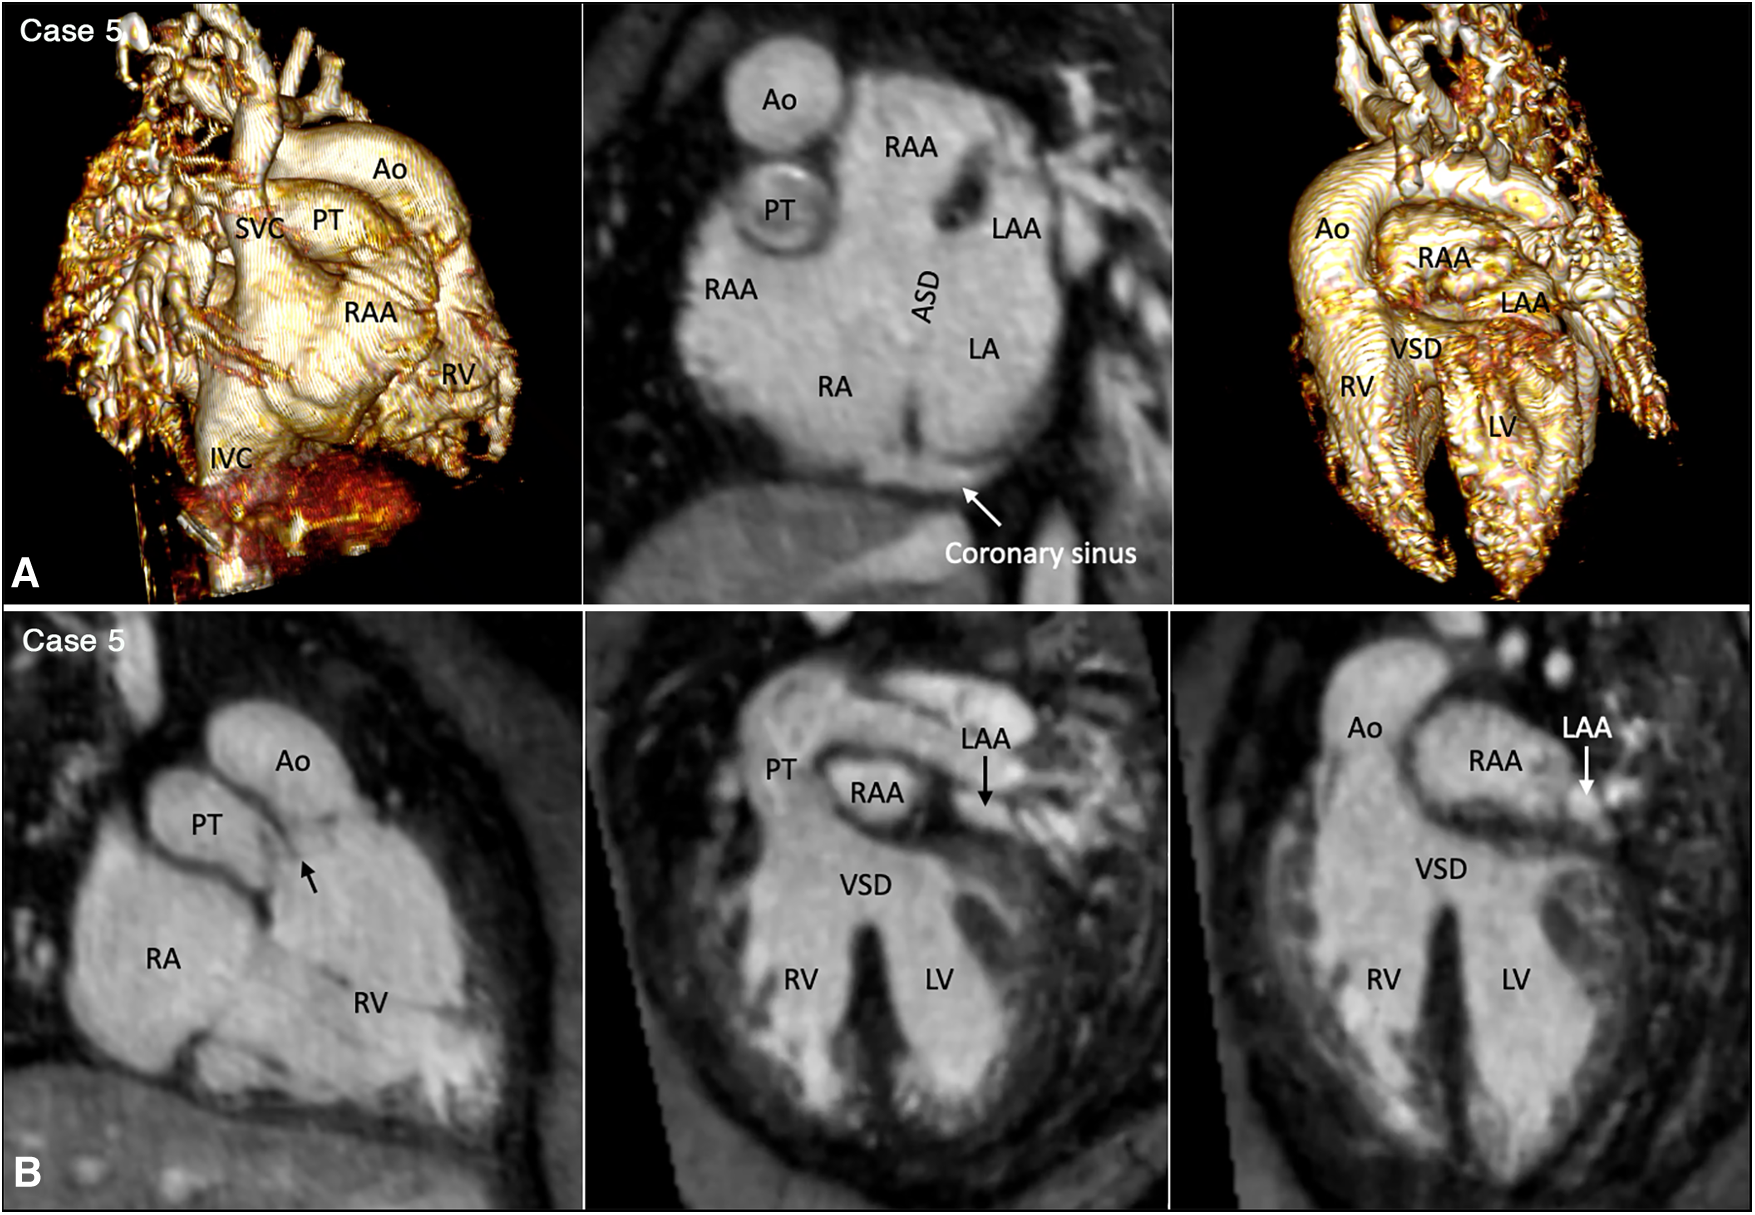

Figure 3

(Case 5). Partial left juxtaposition of the atrial appendages in a patient with situs solitus, concordant atrioventricular connection and double outlet right ventricle. (A) Atrial appendages shown in volume rendered (VR) images taken in oblique views (left and right panels) and maximum intensity projection (MIP) images in short axis plane (middle panel). A part of the right atrial appendage (RAA) is displaced to the left side to lie above and medial to the left atrial appendage (LAA). There is a large atrial septal defect (ASD) in the obliquely oriented atrial septum. (B) MIP images obtained in right anterior oblique view of the right ventricle (left panel) and long axial oblique views of the ventricles (middle and right panels) showing double outlet right ventricle (RV) with a large ventricular septal defect (VSD) at a distance from the valves of the pulmonary arterial trunk (PT) and aorta (Ao). The aortic valve is supported by a long muscular infundibulum and the pulmonary valve is supported by a short muscular infundibulum. The aortic and pulmonary valves are in fibrous continuity above the vestigial outlet septum (arrow in left panel). IVC, inferior vena cava; LA, left atrium; LV, left ventricle; RA, right atrium; SVC, superior vena cava.